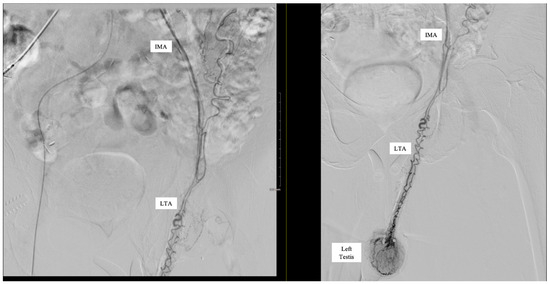

Aberrant Left Testicular Artery Originating from the Inferior Mesenteric Artery Identified on Angiography in a Patient with Gastrointestinal Bleeding: Case Report

| LTA | Left Testicular Artery |

| IMA | Inferior Mesenteric Artery |